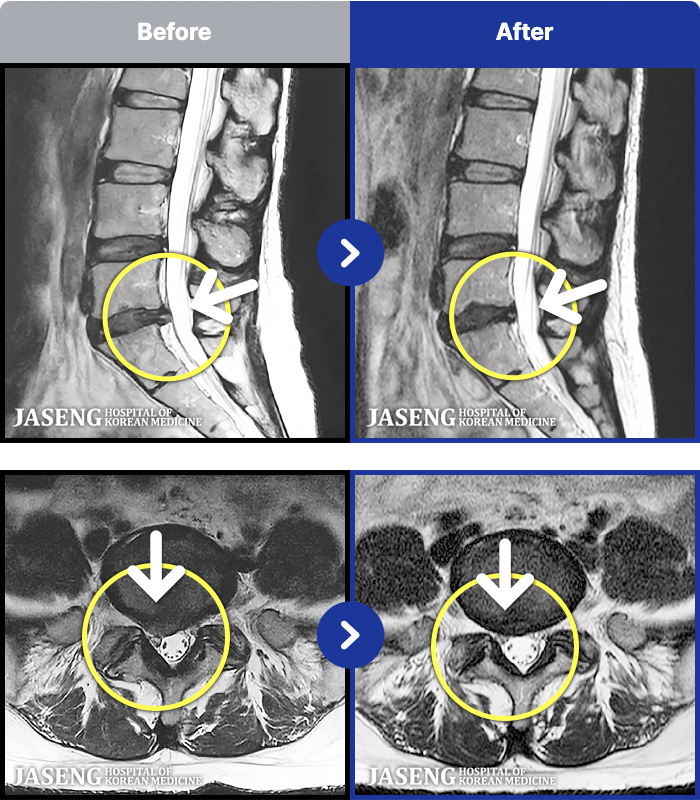

- MRI ġ

MRI ġ

1,237 MRI ũ ʸ Ȯϼ.